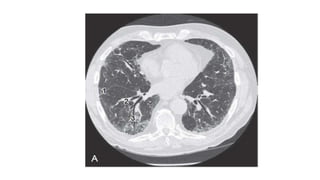

• Chest radiographs typically show basal-predominant reticular

• The diagnostic features on HRCT are peripheral, predominantly basilar

patchy intralobular reticulation, often with subpleural honeycomb

cysts, traction bronchiectasis, and traction bronchiectasis as the

disease becomes more advanced.